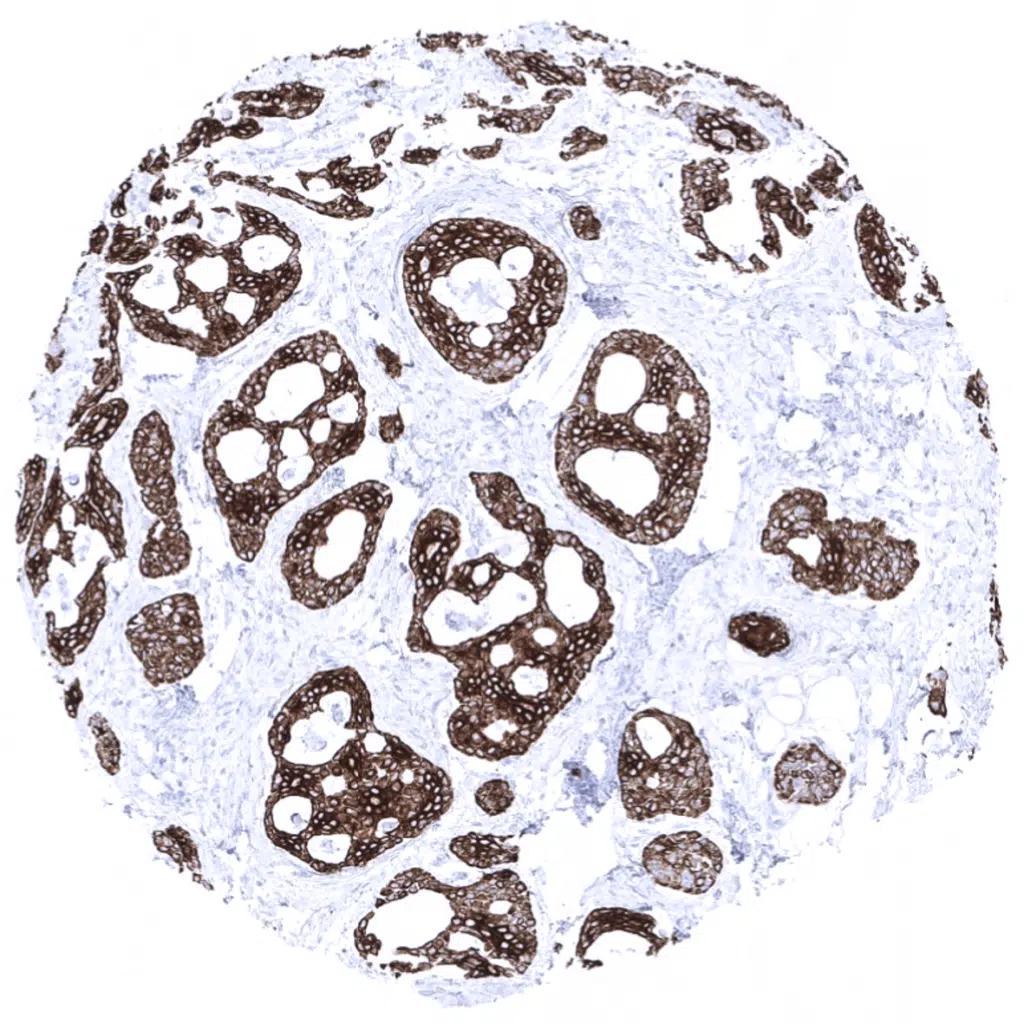

Malignant mesothelioma exhibiting a strong Cytokeratin 5 expression in all epitheloid cells.

Malignant mesothelioma showing Cytokeratin 5 immunostaining of variable intensity in most epitheloid cells.

Strong Cytokeratin 5 expression in all epitheloid cells of a malignant mesothelioma.